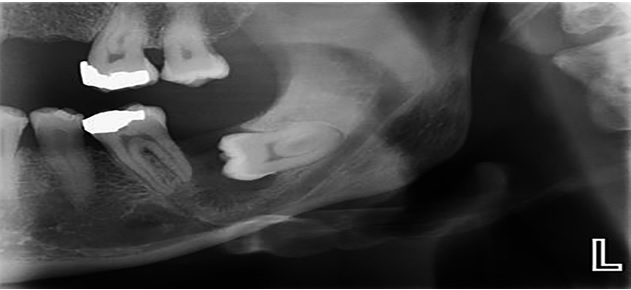

Viêm quanh răng và tiêu xương ổ răng: Răng khôn mọc lệch cũng có thể làm tăng nguy cơ viêm quanh răng ở vùng phía sau cung hàm. Vi khuẩn tích tụ lâu ngày gây viêm nướu, phá hủy mô nâng đỡ răng và dẫn đến tiêu xương ổ răng. Nếu không được phát hiện sớm, tình trạng này có thể khiến răng kế cận bị lung lay hoặc mất răng.

.jpg)

Hình ảnh răng khôn mọc lệch gây viêm quanh răng và tiêu xương ổ răng